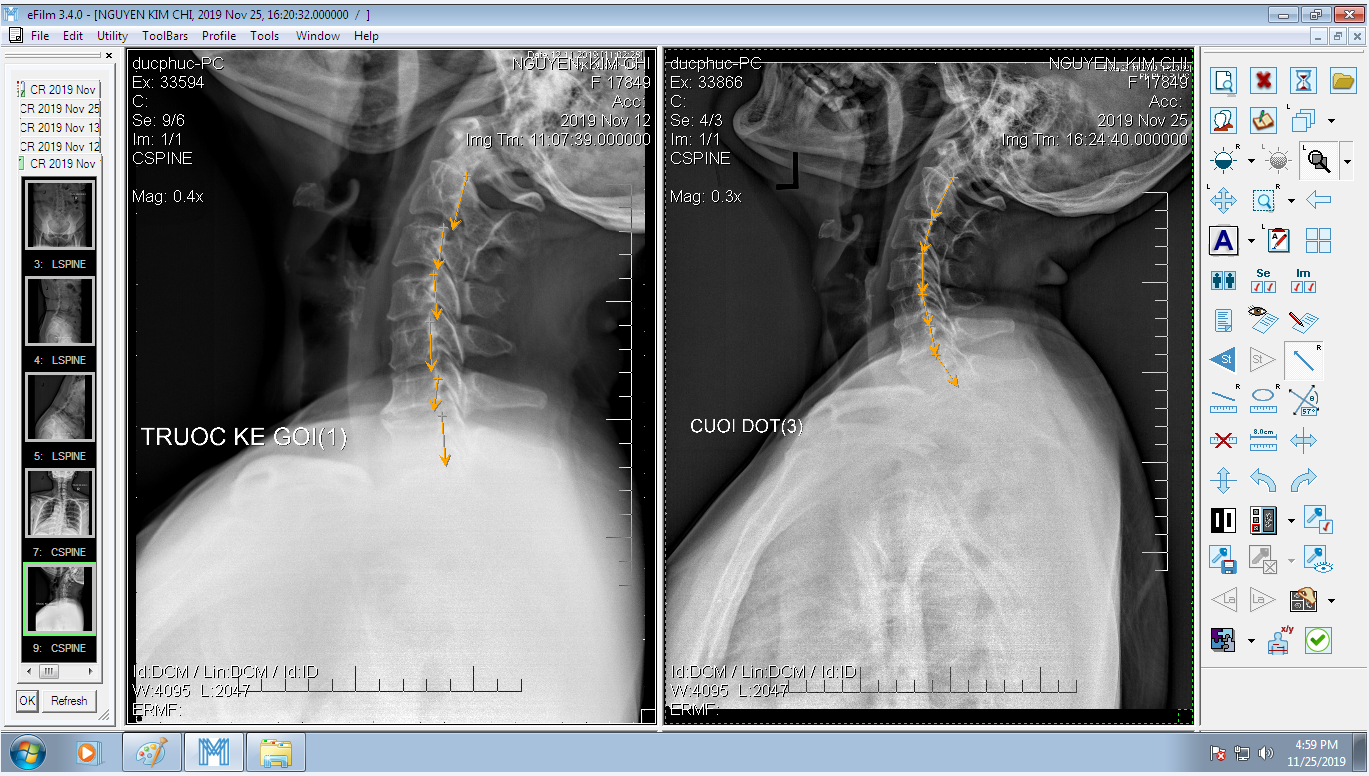

DOCTORLOAN đã thành công trong điều chỉnh xương khớp về đúng vị trí trong thời gian ngắn